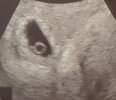

mamy pęcherzyk ciążowy w macicy i pęcherzyk żółtkowy. Kolejna wizyta w poniedziałek. Mam wrażenie, że na końcu pęcherzyka żółtkowego pojawia się mały „cosiek”, ale pani doktor jeszcze nic nie potwierdziła

była bardzo zachowawcza- moja historia niestety pozostawia wiele do życzenia